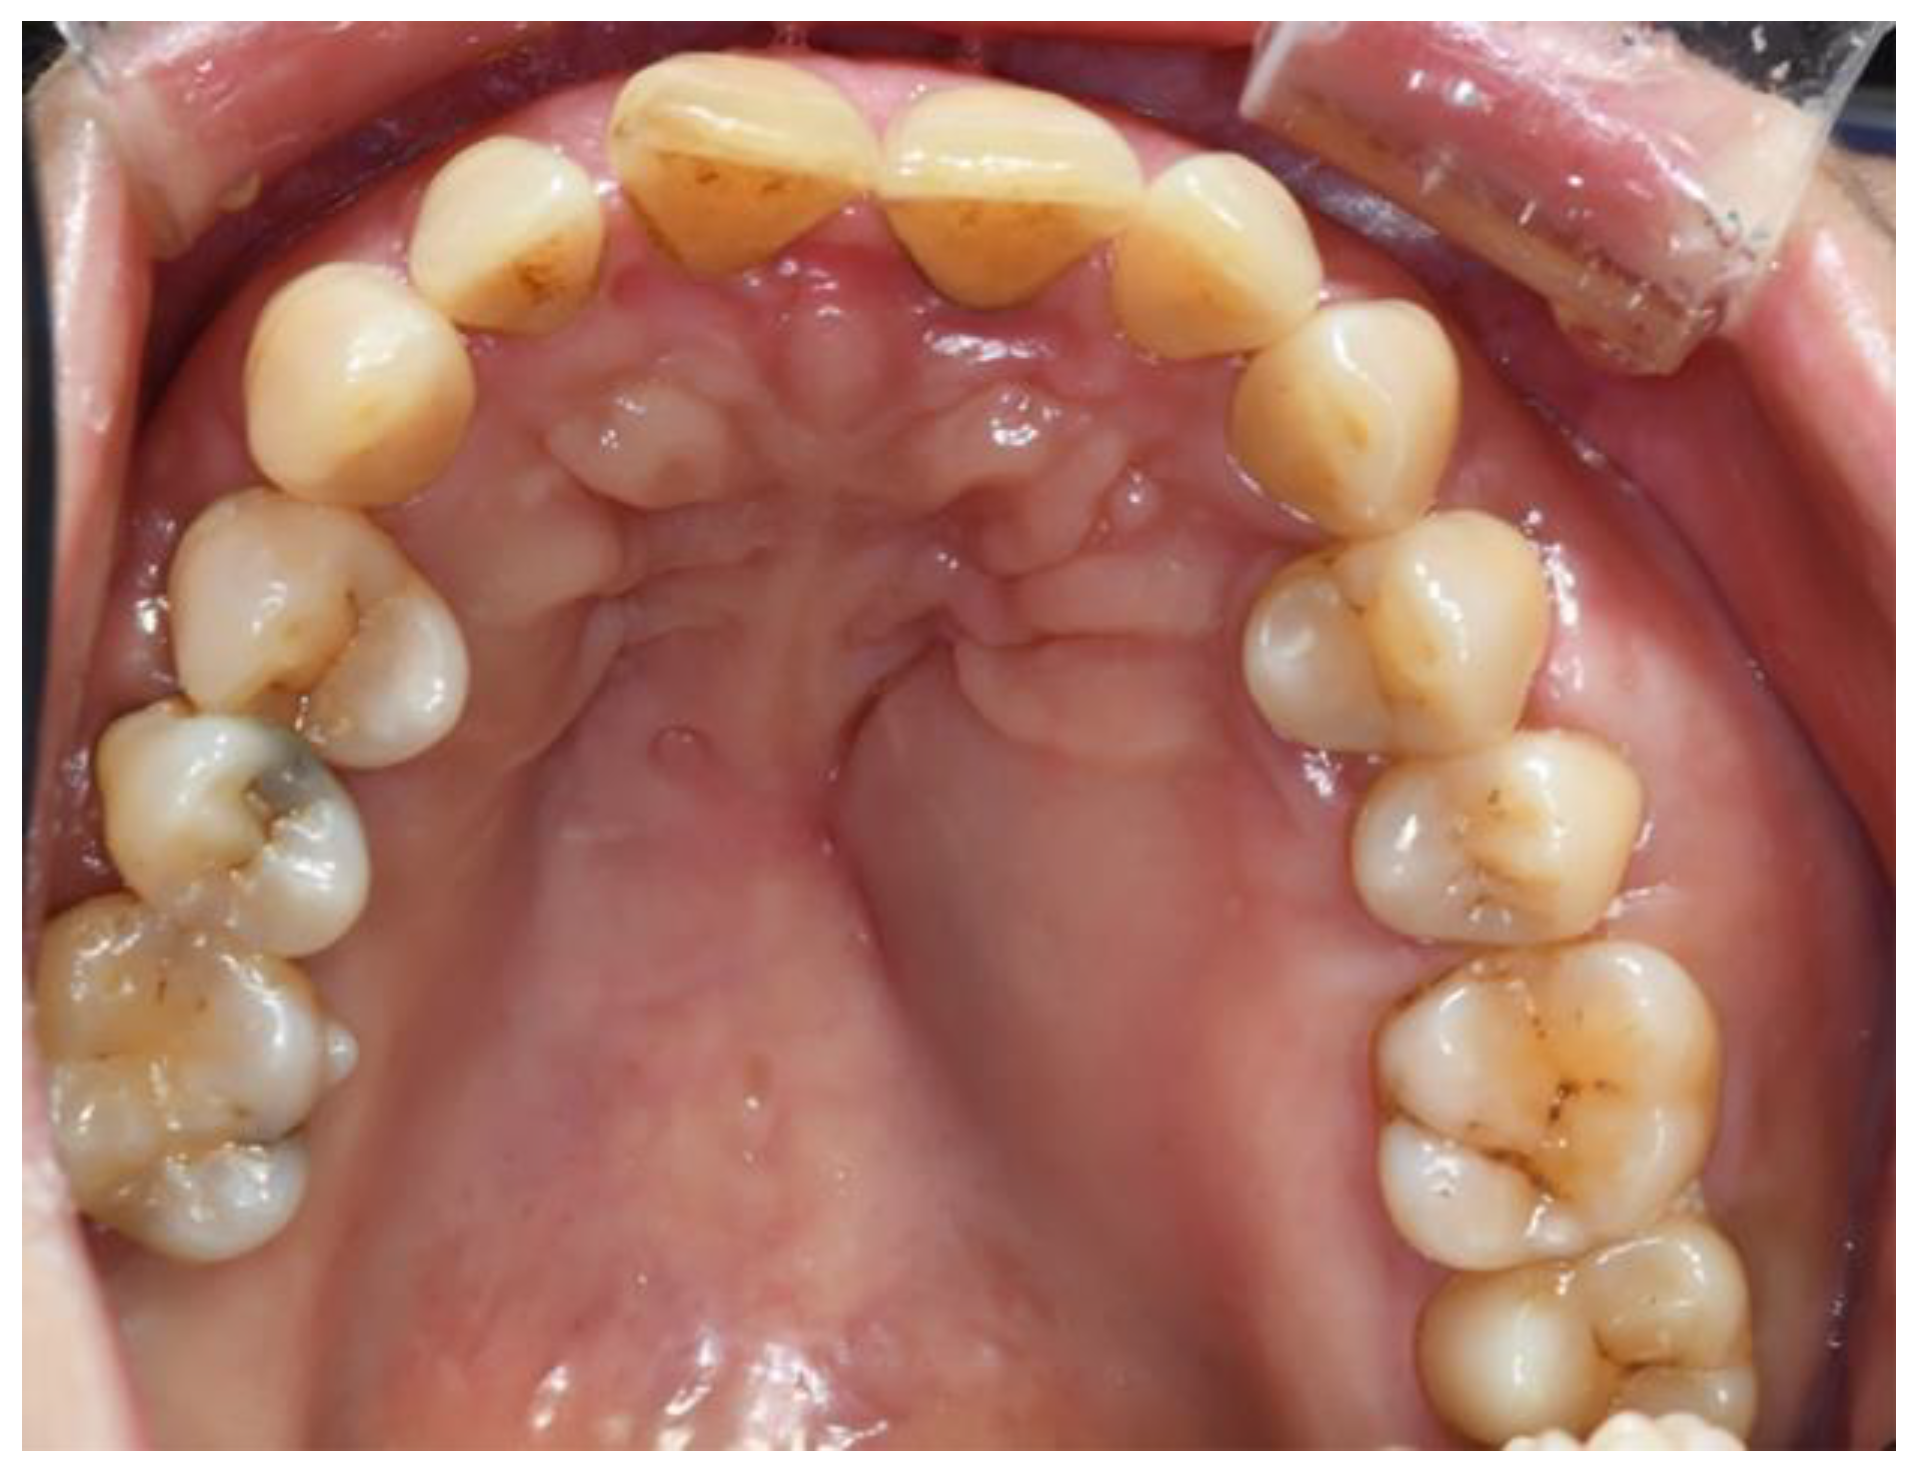

2.1. Clinical Presentation